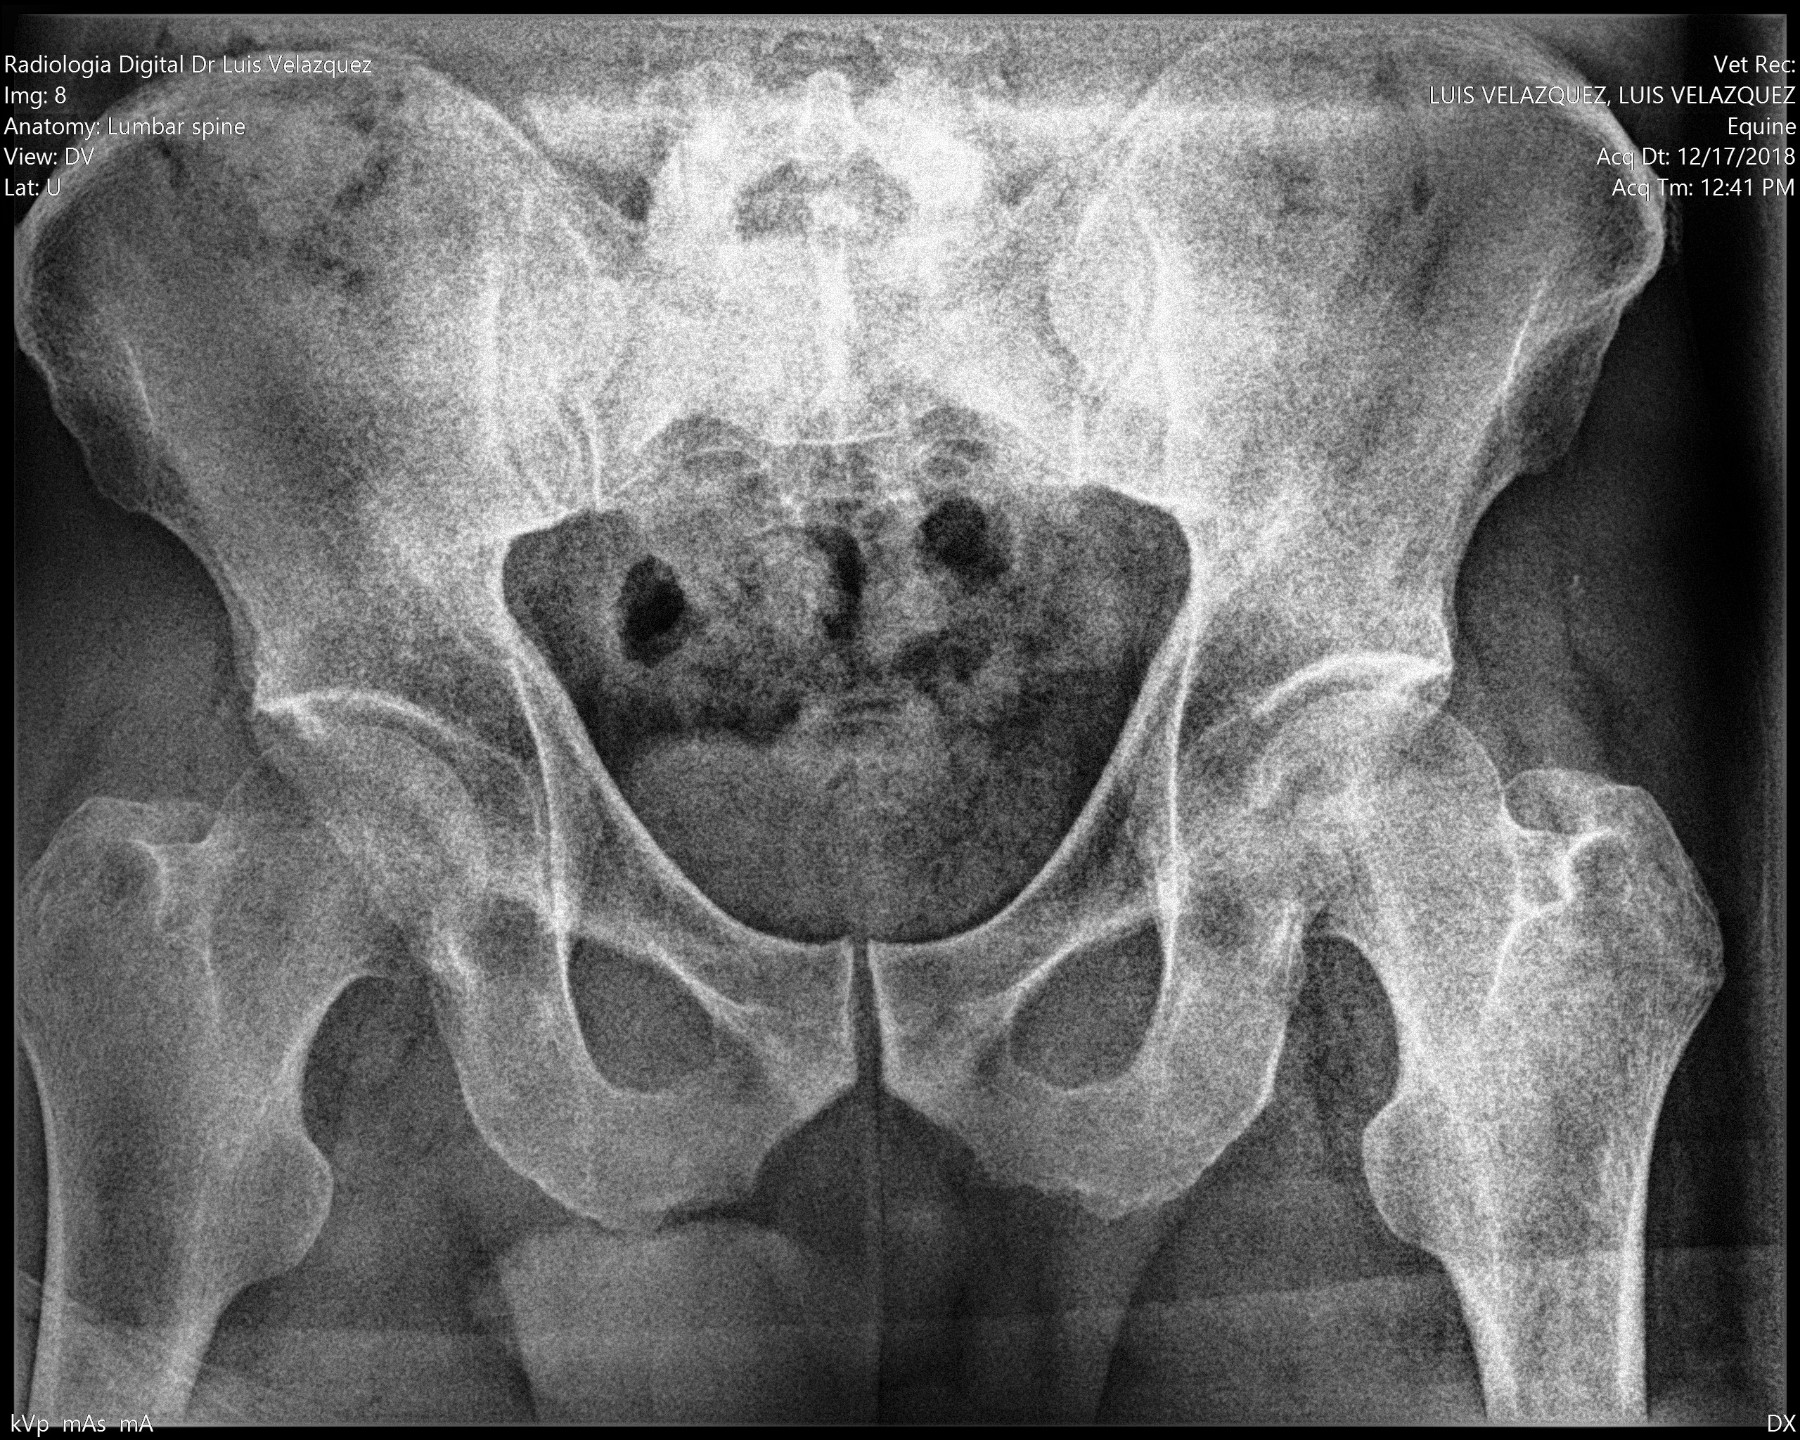

Cambios Térmicos en las Extremidades de Caballos,

Asociados a Golpes y su Evaluación por Termografía.

Los caballos de salto, en competencia, pueden derribar obstáculos y lastimarse. Si se golpean, no siempre claudican. Considerando al calor como un signo de inflamación, se evaluaron los cambios térmicos de 6 áreas de las extremidades torácicas y pelvianas de 23 caballos de salto en nivel de competencia de 1.05 a 1.60 m de altura, por medio de termografía durante 4 días de competencia (N=2208 áreas).